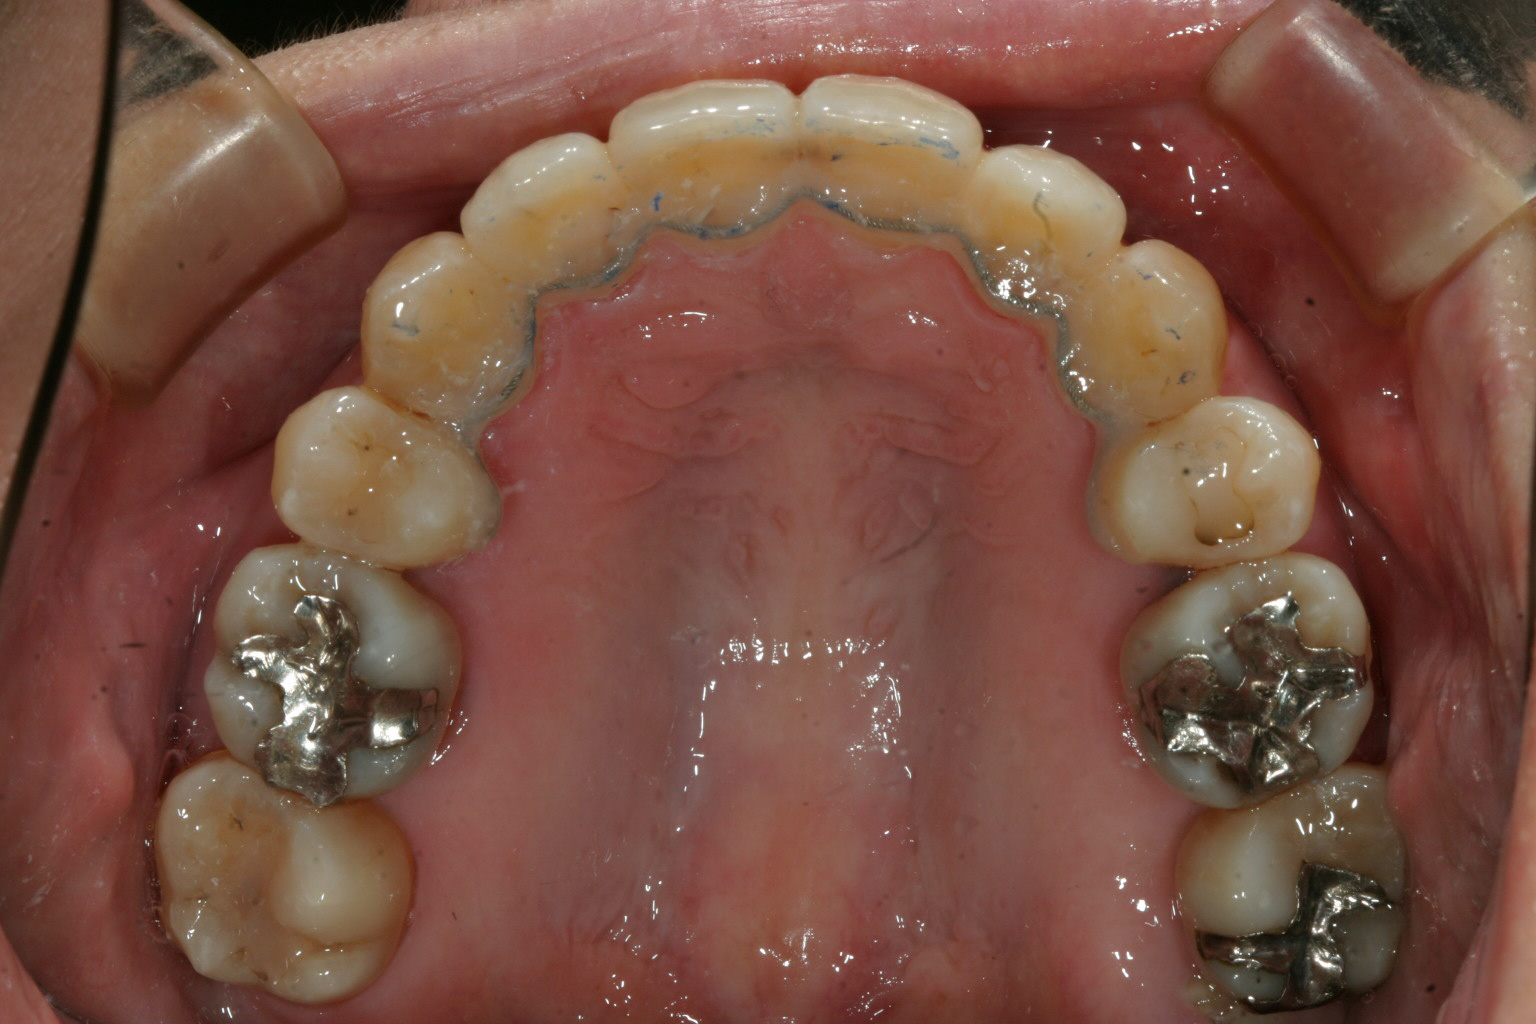

小臼歯抜歯した後に綺麗に犬歯が入りました。

上下左右の小臼歯抜歯してインビザラインと加速矯正装置利用で矯正しました。

かなり綺麗に仕上がりました。

途中で抜歯スペース閉鎖する時に後ろの歯が前に倒れて来て立てるのに部分ワイヤー矯正も併用し少し時間を食いましたが一切追加費用無しで終了しました。